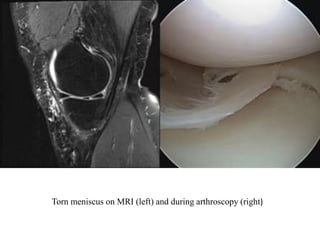

Normal meniscus on MRI (left) and during arthroscopy (right)

Torn meniscus on MRI (left) and during arthroscopy (right)

Normal meniscus onMRI (left) and during arthroscopy (right)

Torn meniscus onMRI (left) and during arthroscopy (right)

• #23 Normally the medal and lateral menisci appear as low signal bow-tie-shaped structures between the femoral condyles and tibial plateauxThe absent bow tie sign represents the loss of the normal appearance of the menisci on parasagittal MRI images, and is suggestive of meniscal injury.

• #27 The double PCL sign appears on sagittal MRI images of the knee when there is a bucket-handle tear of the meniscus